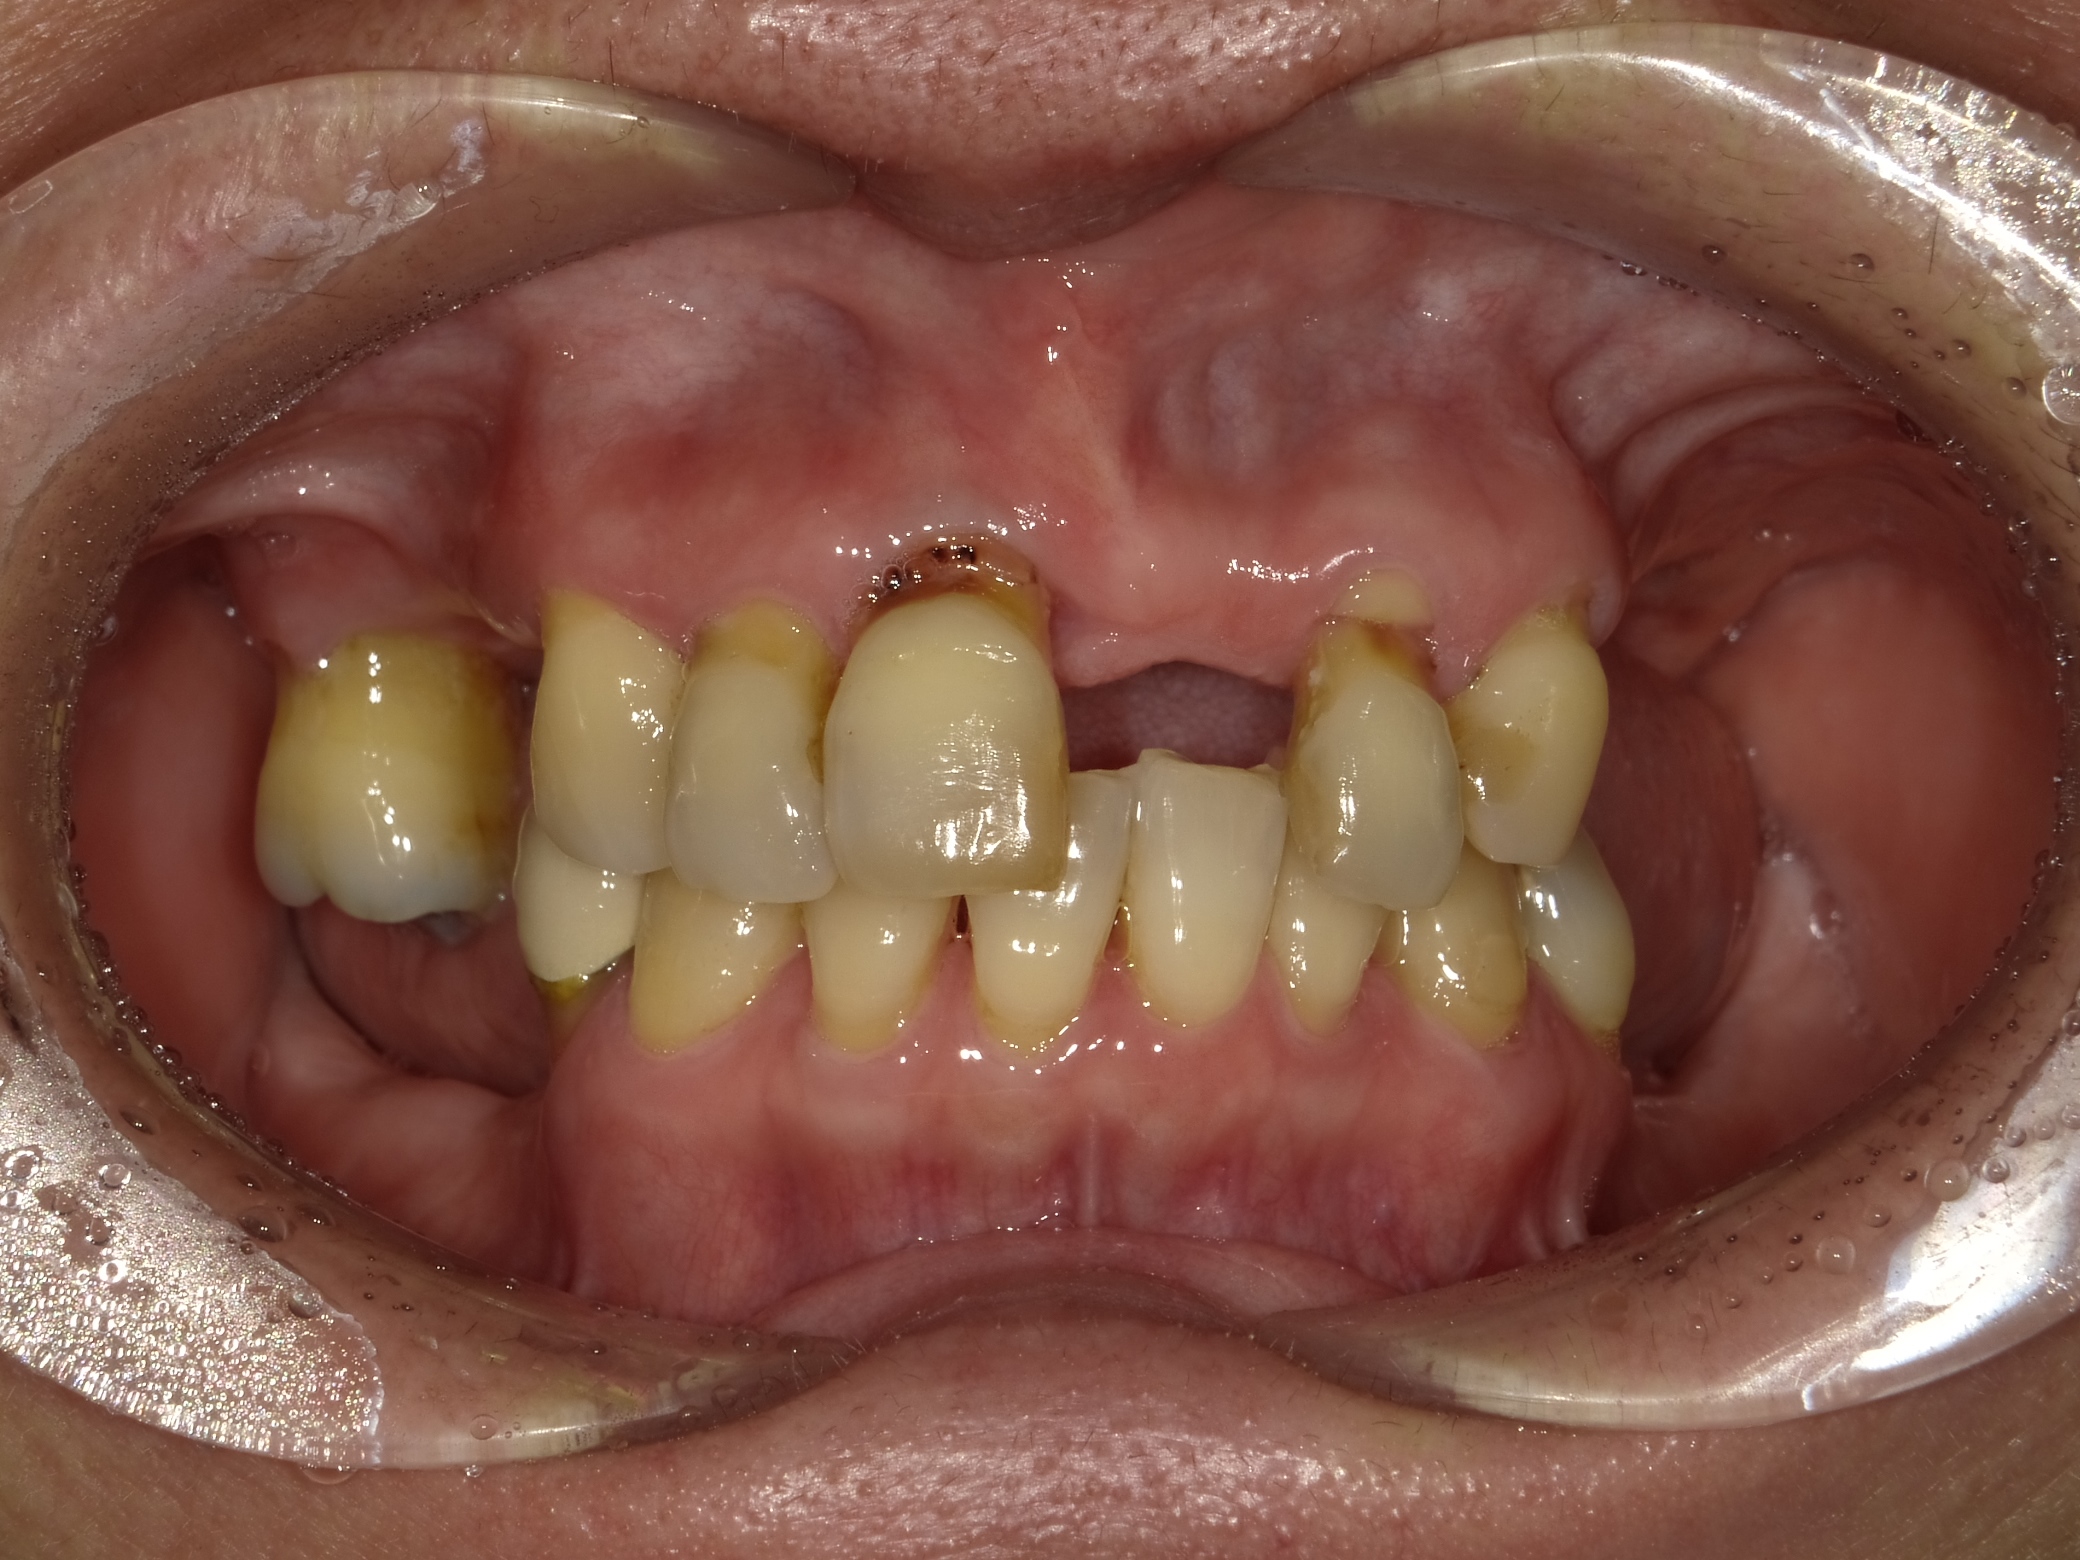

BEFORE

主訴

全体的に見た目を綺麗にしたい。奥歯でしっかり噛みたい。

診断名・主な症状

臼歯部欠損

年齢

65歳

治療内容

インプラント埋入(左下5・6,右下5・6,左上4・6)

サイナスリフト(左上4・6)

ジルコニアBr(右上6−左上3)

E –MAX CAD(右下4)

セラミックインレー(左下4)

治療期間/

通院回数

約1.5年/約20回

費用

インプラント治療 約2,000,000円

その他被せ物治療など 約1,000,000円

合計 約3,000,000円

*いずれも税込